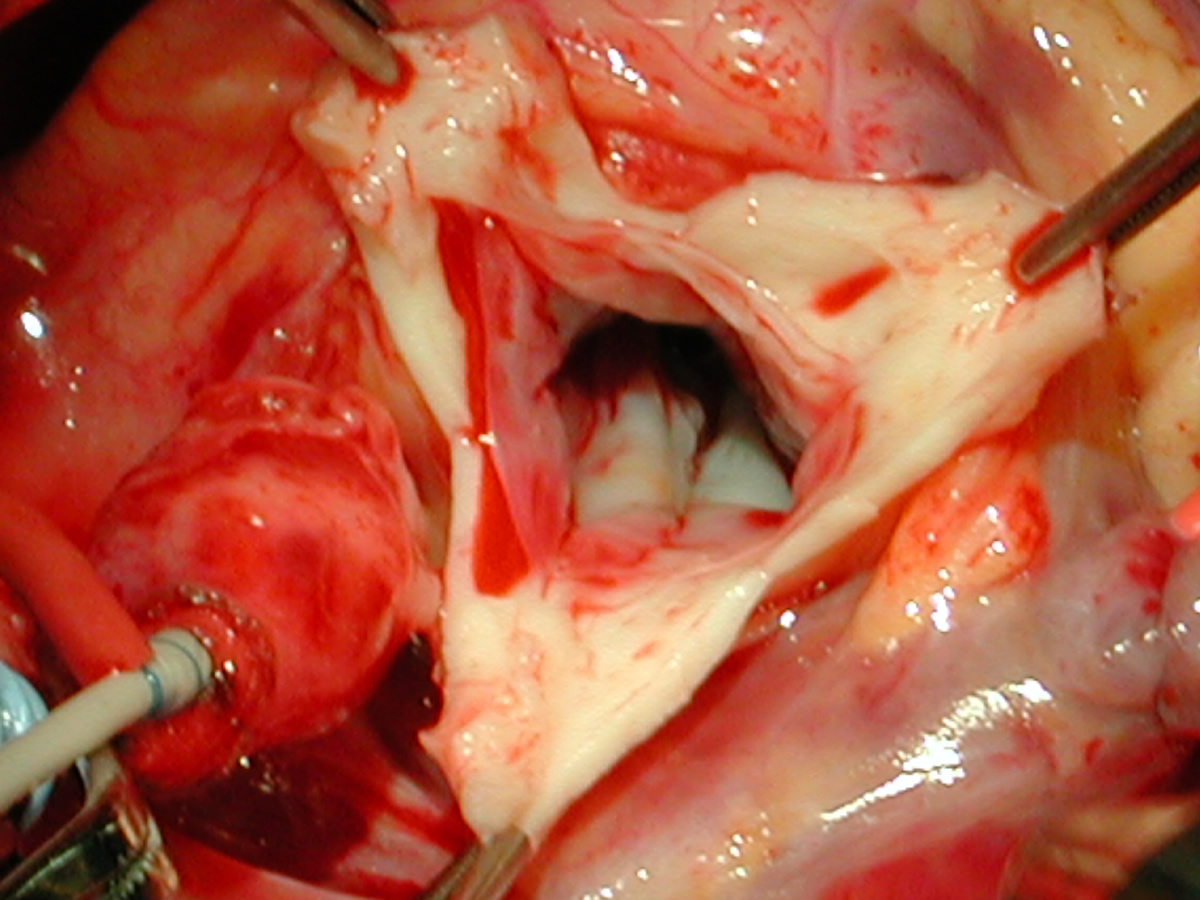

The operative approach is through a median sternotomy with the use of cardiopulmonary bypass and bicaval venous cannulation. The first dose of cold blood cardioplegia is antegrade; the remaining doses are retrograde.

High ascending aortic cannulation adjacent to the innominate artery for maximum exposure of the ascending aorta and to allow length for positioning of the patch in the ascending aorta.

One dose of antegrade cardioplegia followed by retrograde cardioplegia.

Pulmonary homograft or pericardial patches (tanned in glutaraldehyde) for the “shields”. These patches should not be too large – this will lead to aortic insufficiency.

First coronary sinus incision in noncoronary sinus to facilitate exposure of the incisions into the coronary orifice sinuses.

In most cases, the right coronary artery sinus should be opened to the left of the coronary orifice and the left coronary artery sinus to the right of the coronary orifice. Occasionally one may not have enough room between a coronary orifice and the aortic valve; in this case the incision site should be tailored to the situation.

Ensure similar orifice sizes between the proximal and distal ascending aorta after patch augmentation by the use of a sizing dilator.

Transesophageal echocardiography to assess completeness of repair, coronary blood flow postoperatively, wall motion abnormalities, and adequacy of aortic valve.